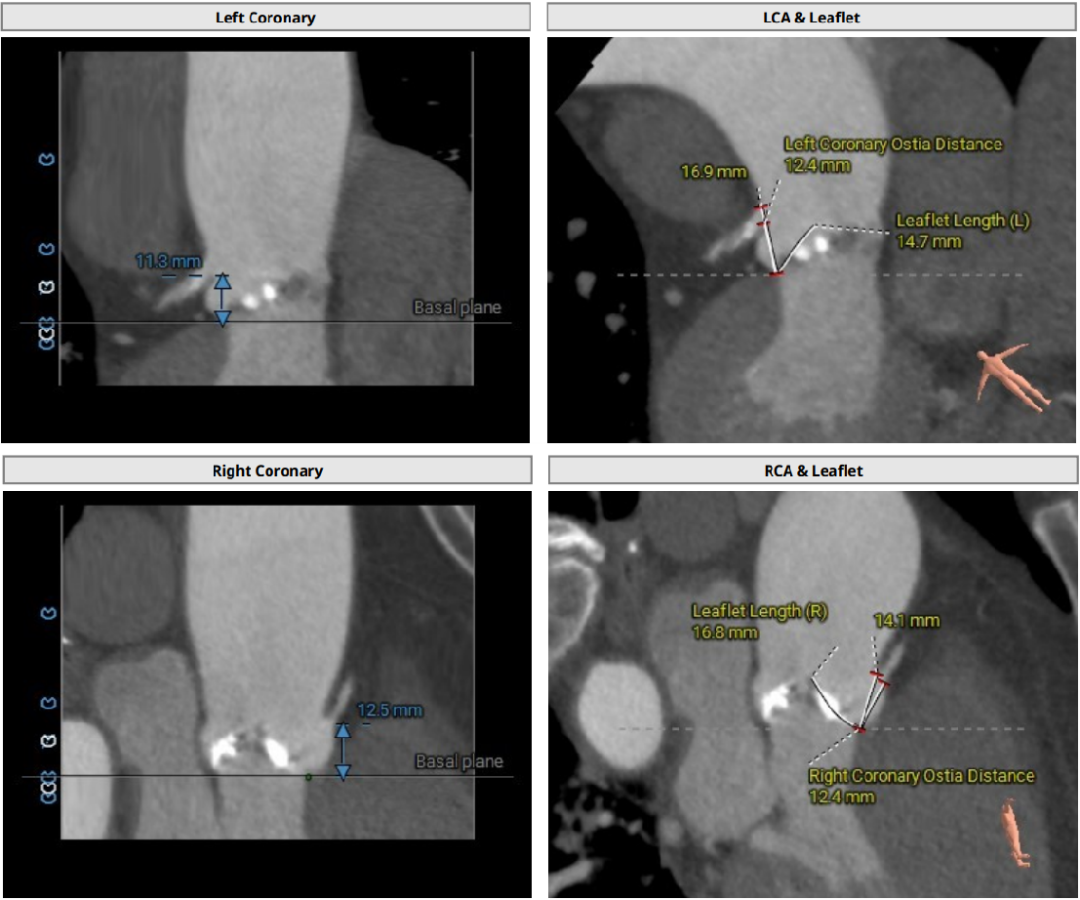

Type1型二叶式主动脉瓣,瓣叶增厚,L-R钙化融合嵴,左冠瓣及无冠瓣对合缘局部钙化,并可见无冠窦向左室流出道延伸长钙化;左室流出道呈微敞口型;

左冠开口偏低,右冠脉开口高度尚可,左右冠瓣叶冗长,切线位测量左右冠瓣叶长度>瓣叶附着缘到冠脉开口距离;左主干及回旋支局部钙化;

冠脉阻挡风险及左室大小评估

左右冠脉开口高度尚可,左右冠瓣叶冗长,切线位测量瓣叶大于冠脉开口下缘距离;左主干及回旋支局部钙化,综合评估瓦式窦内径及L-R融合嵴、瓣叶钙化等结构影响,植入瓣膜后冠脉风险适中;